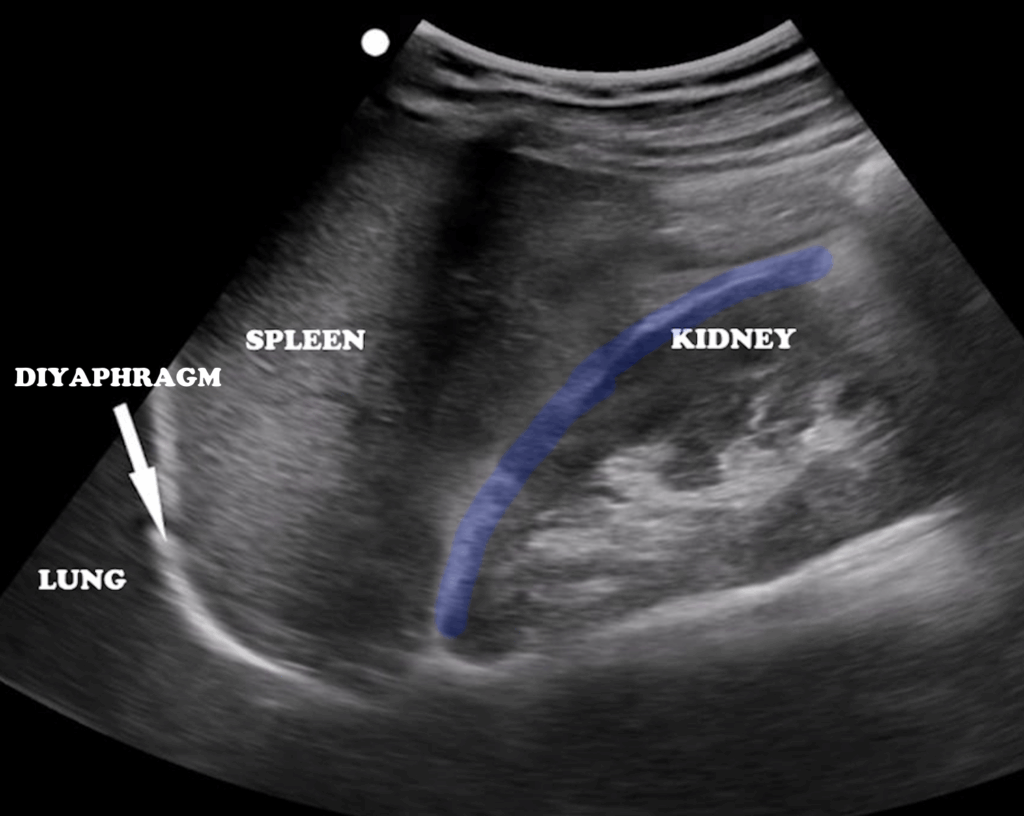

The spleen is located in the left upper abdominal quadrant, just beneath the diaphragm. Its anatomical relations are as follows: superiorly the diaphragm, anteriorly the fundus of the stomach, posteriorly the left kidney, and medially the tail of the pancreas (Figure 13). Compared to the liver, the spleen appears more hyperechoic and homogeneous. Its average dimensions are 10 cm in length, 7–8 cm in width, and 4.5 cm in thickness. For imaging, the patient lies in a supine position, and the probe is placed along the posterior axillary line through the left lower intercostal spaces. Disruption of the homogeneous echotexture is significant for identifying lacerations due to trauma (Figure 14), infarction, or the presence of perisplenic fluid.